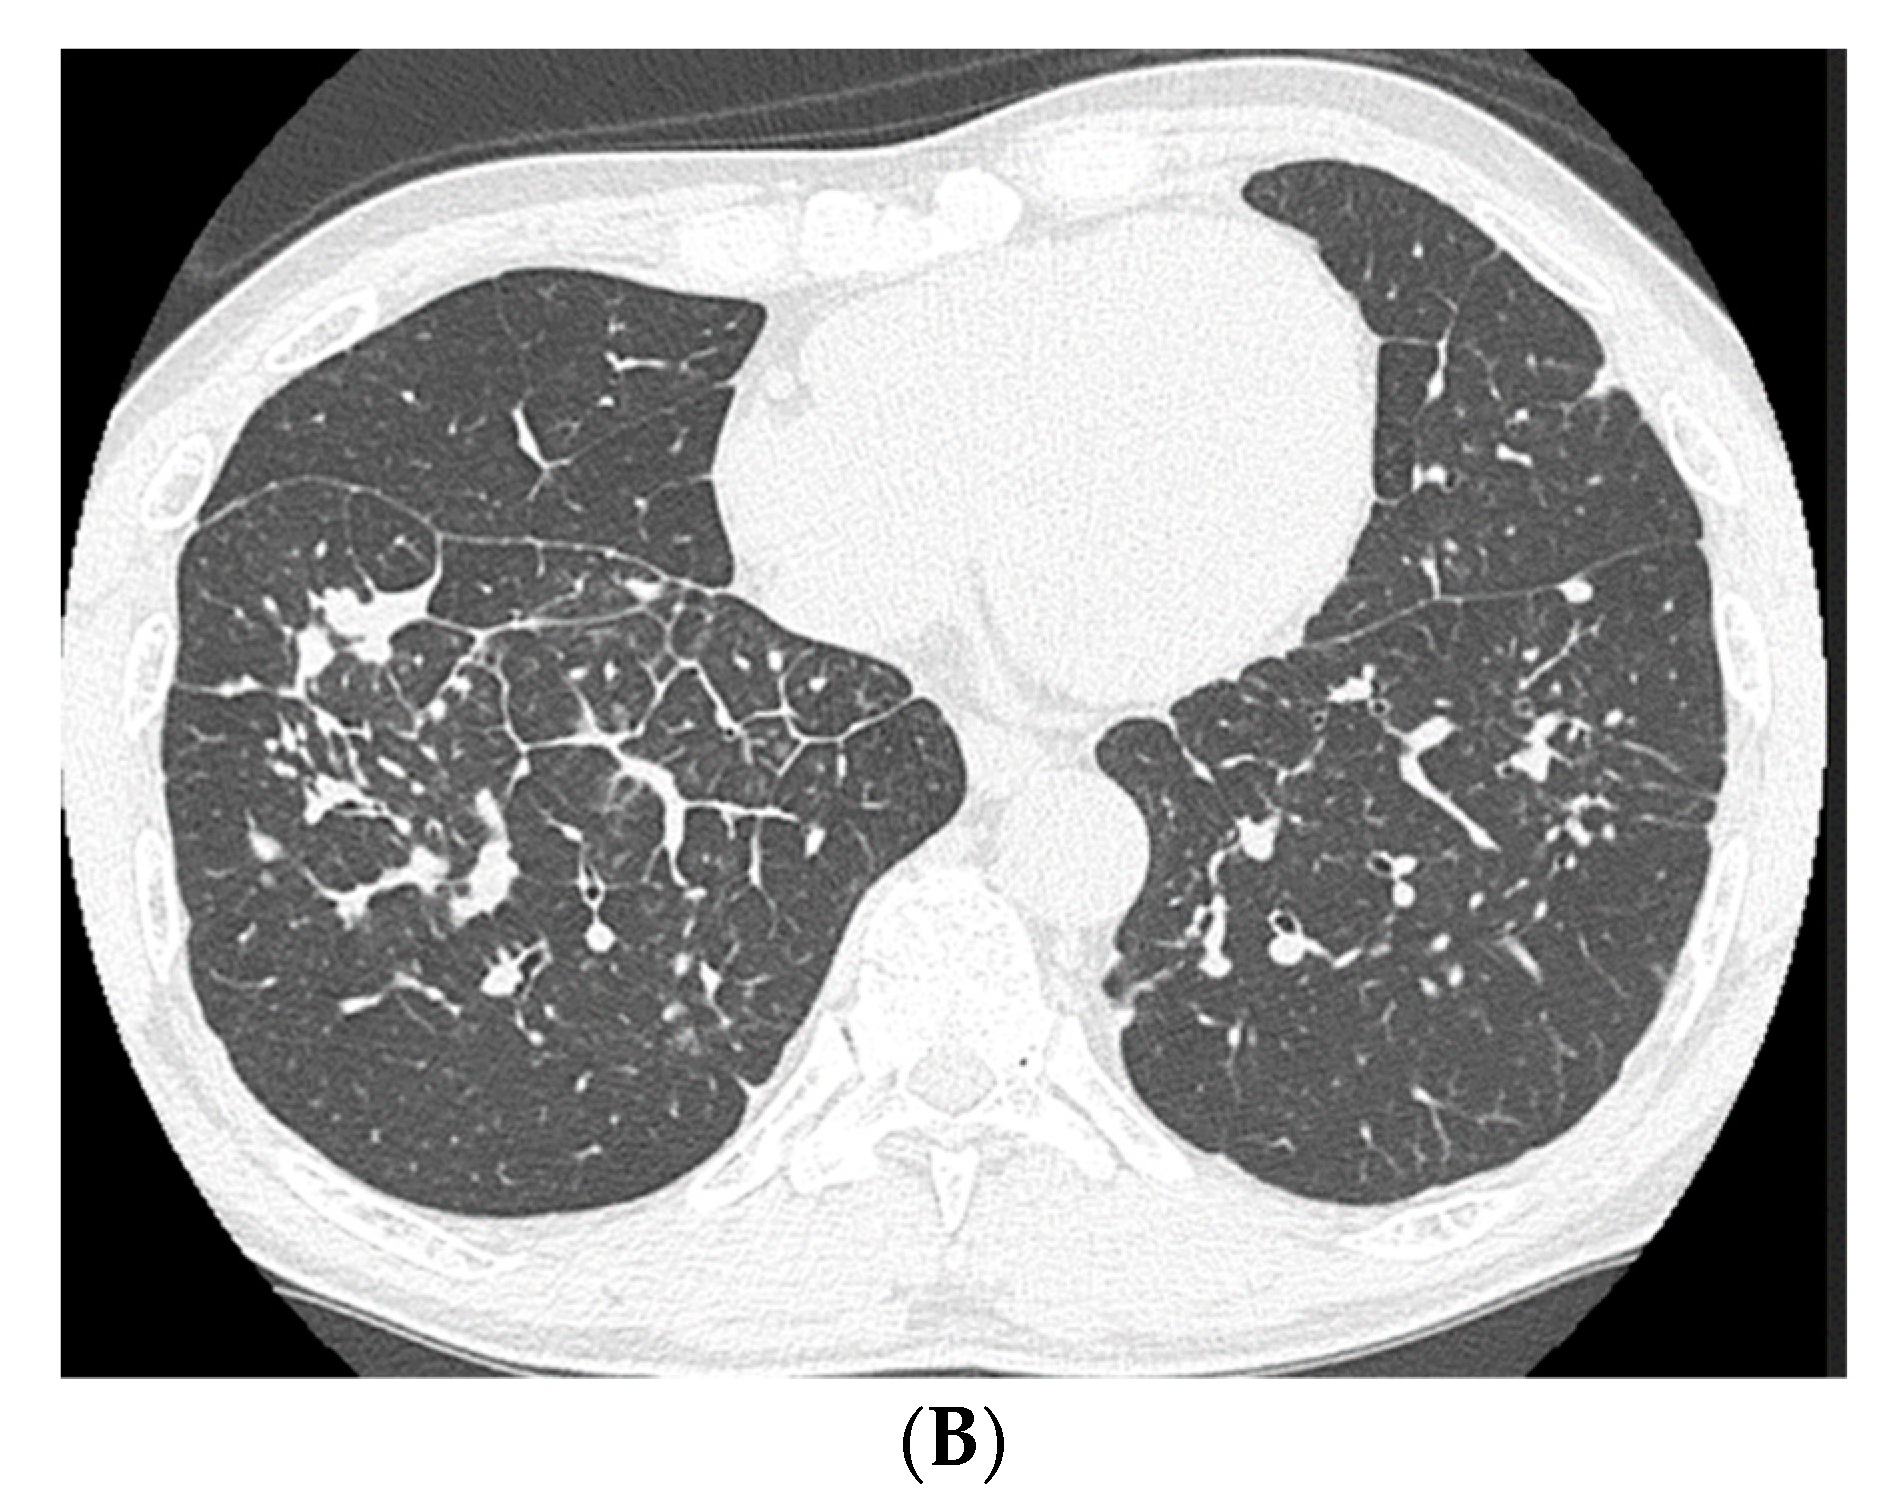

High-resolution computed tomography (HRCT) (Figure 2) showed well-defined multiple centrilobular and perilobular nodules, and thickening of the intralobular septa in the middle and lower zones of both lungs. No pleural effusion or mediastinal lymphadenopathy was observed.

Figure 2.

High-resolution computed tomography of the lower lung lobes on admission, showing well-defined multiple centrilobular and perilobular nodules, and thickening of the intralobular septa in the middle and lower zones of both lungs.